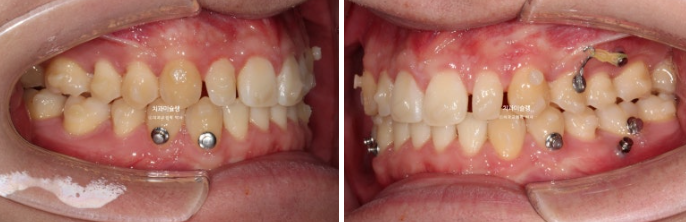

2022년 10월 비대칭으로 내원하신 분입니다.

중심선 불일치, 왜소치로 인한 벌어짐, 송곳니 덧니 등이 보입니다.

이 환자분이 한쪽으로만 씹었던 이유는 반대쪽에 가위교합이 있었기 때문입니다.

파란 화살표가 가위교합이고 위 큰어금니는 바깥으로 나가있고 대합치는 안쪽으로 쓰러지며 가위처럼 서로 엇갈려 교합되는 상태를 말합니다.

파란 화살표 치아가 바깥으로 뻗치면서 가위교합의 원인이 됩니다.